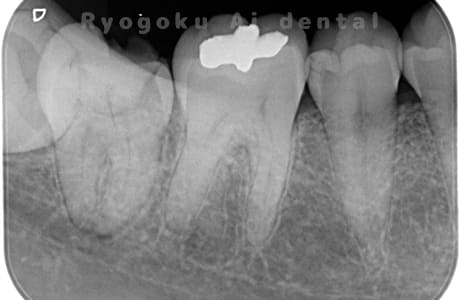

Case10

- 右下6番 重度カリエス

- 右下8を右下6へ移植に自家歯牙移植

- 約1か月半

- 220,000円

右下の銀歯が外れかかっているとのことでご来院された患者様です。虫歯が大きく、かつ歯が割れており、保存不可能と判断し、親知らずの移植を行いました。